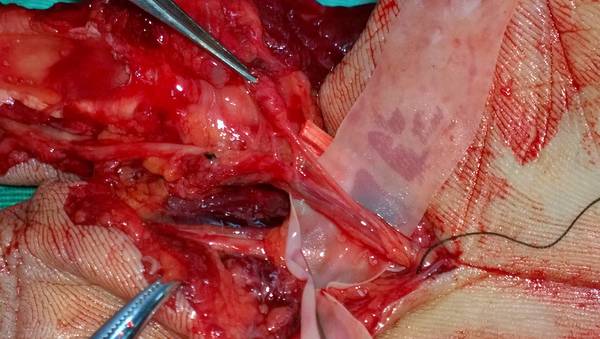

[手指再造] 残指重建拇指

今天上传术中及近期术后的图片

手术设计很漂亮